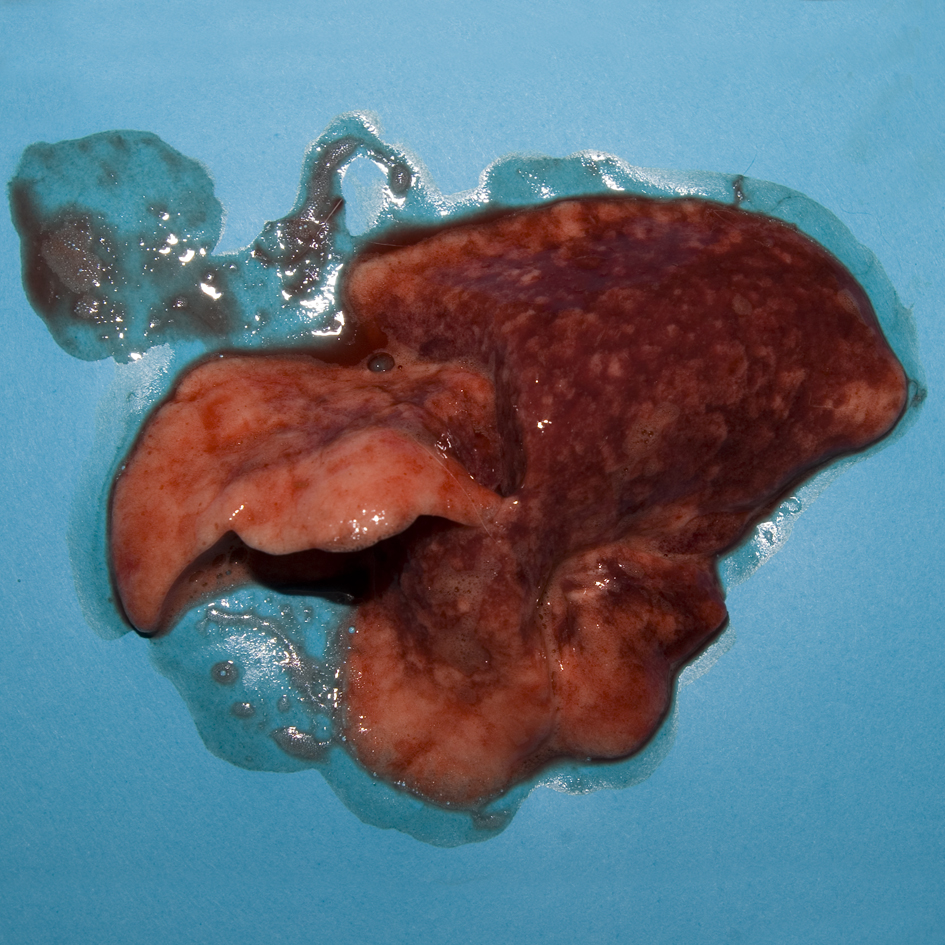

Pulmonary haemorrhage and oedema are features of RHD although, macroscopically, it can be difficult to differentiate agonal changes, such as alveolar collapse, congestion, and alveolar oedema from lung pathology. In this confirmed case of RHD, fibrin thrombi were seen in occasional small capillaries and venules on histopathological examination.